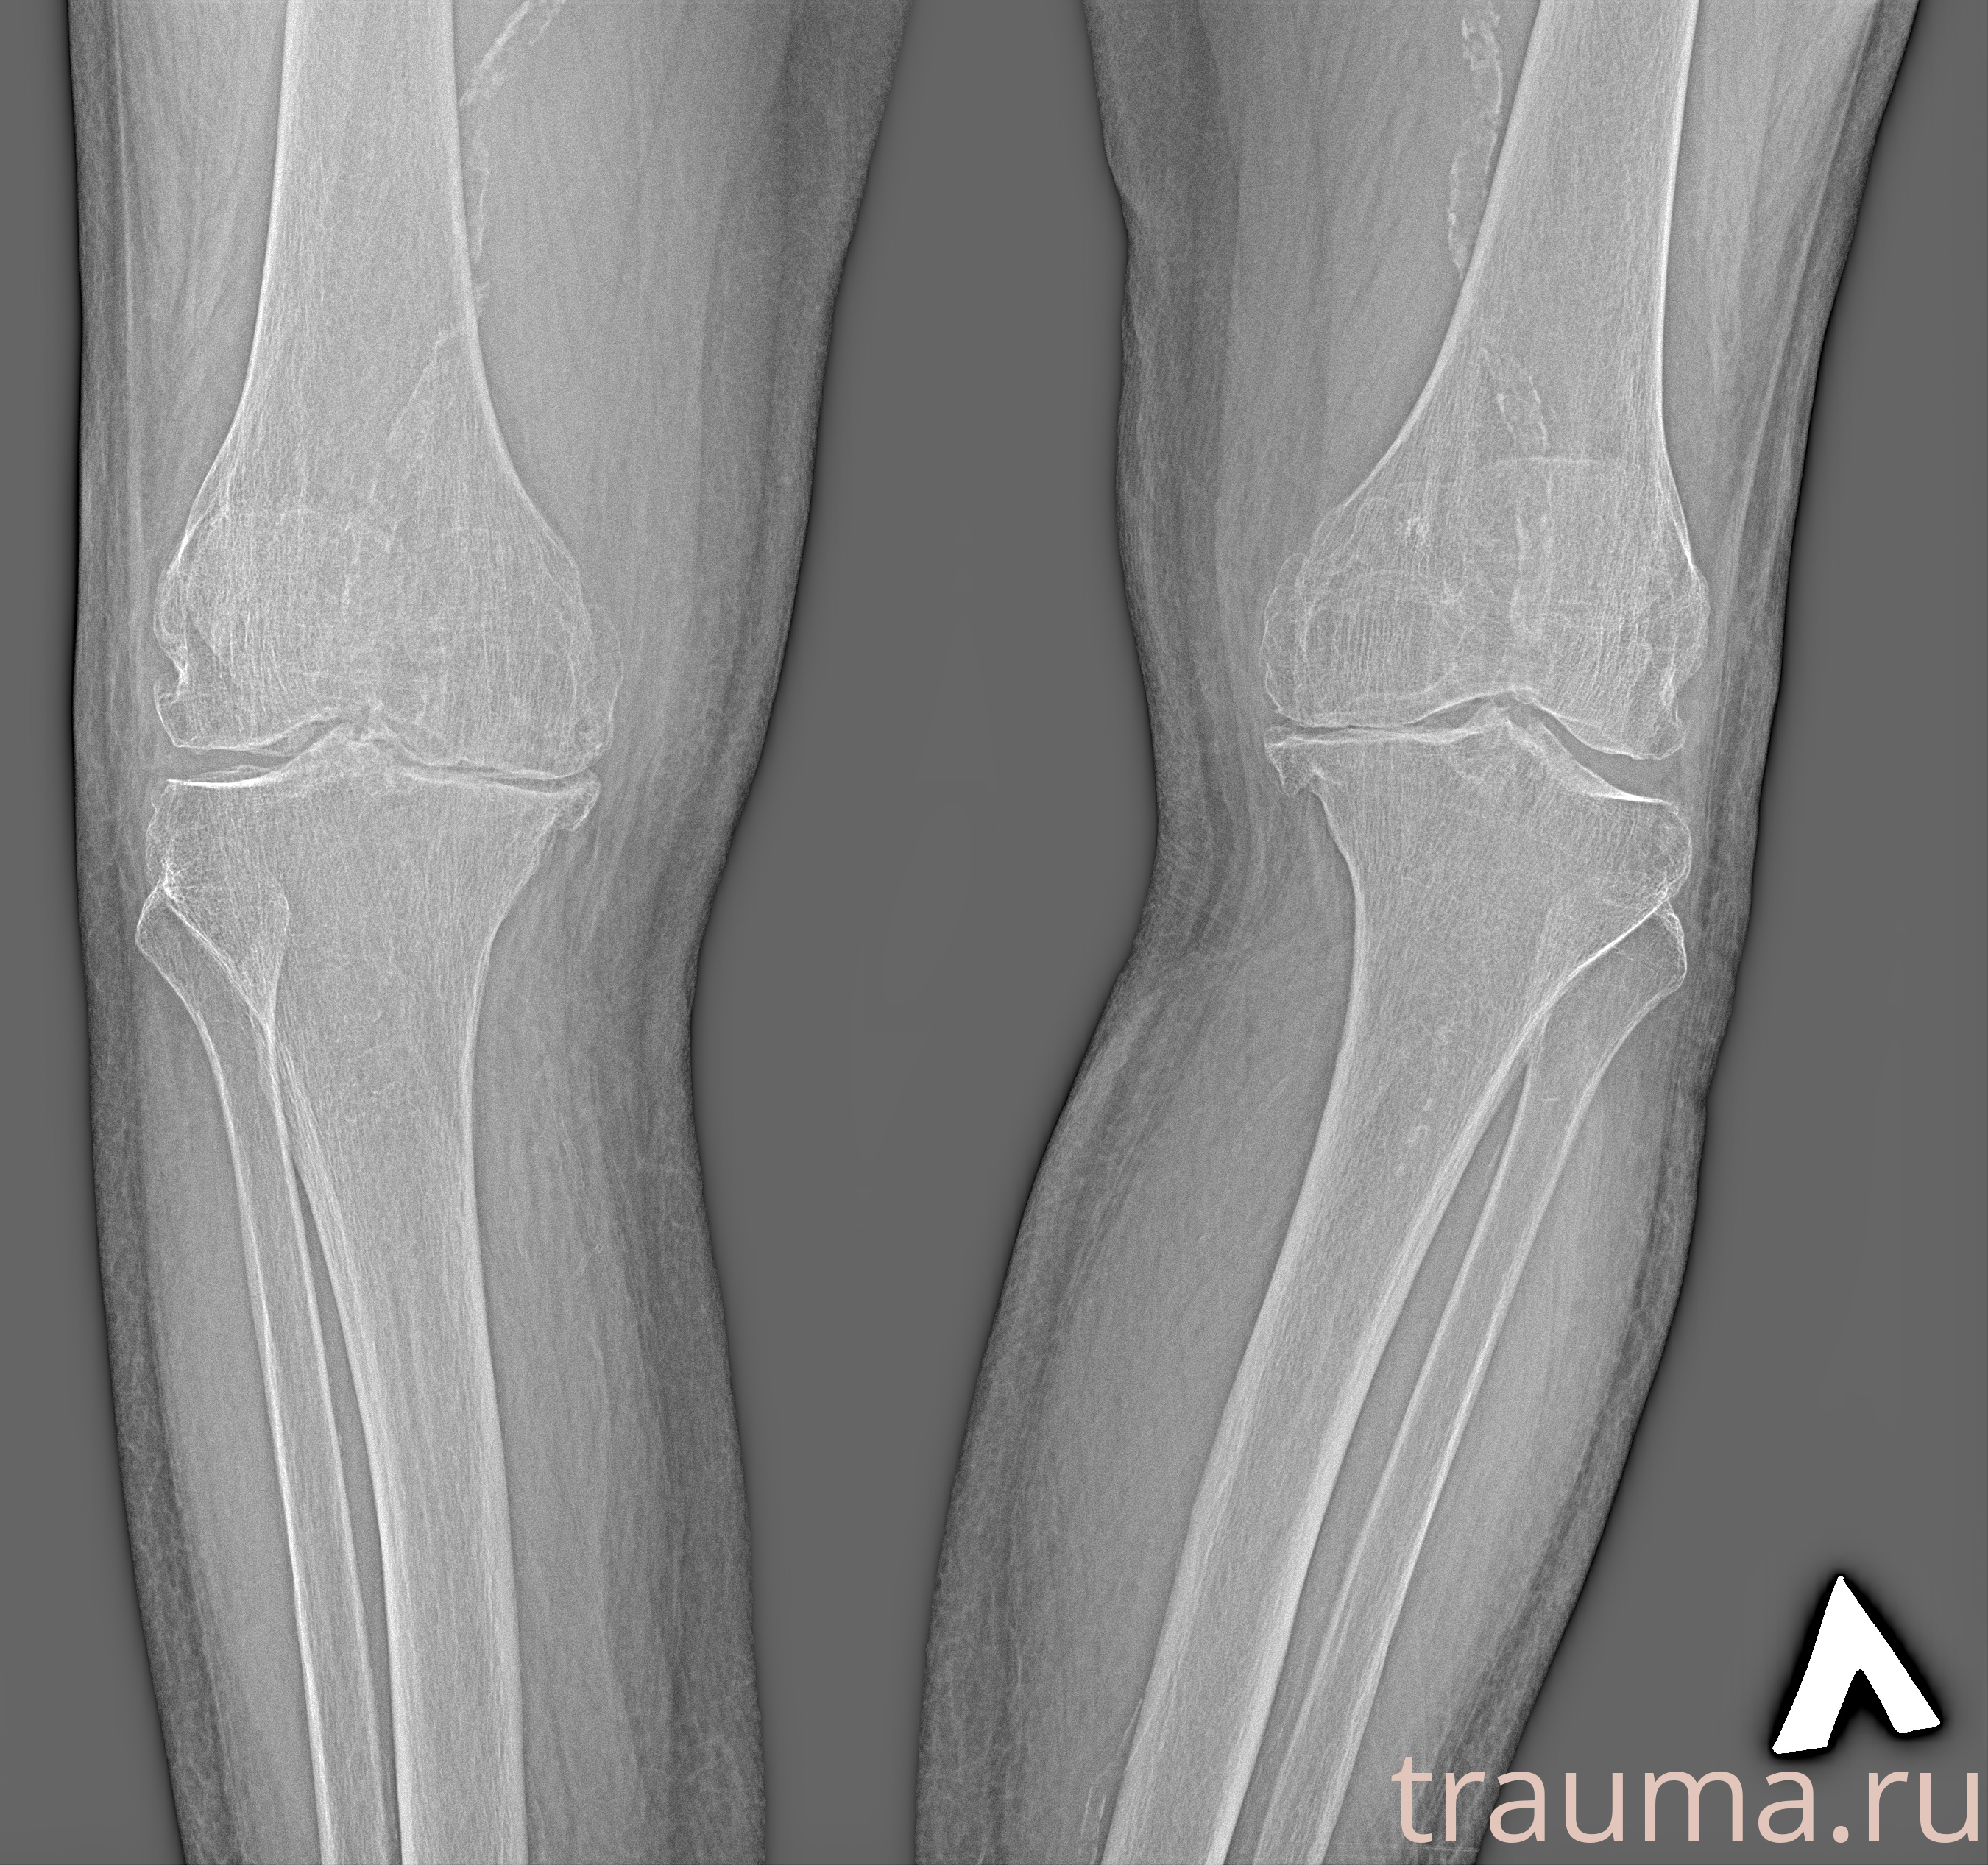

Рентген на дому: по вашему адресу приезжает врач-рентгенолог, травматолог-ортопед с мобильным рентгеновским аппаратом, проводит диагностику травмы или заболевания, делает необходимые рентгенограммы, дает рекомендации по дальнейшему лечению. Получить качественные снимки в домашних условиях возможно благодаря уникальной методике, разработанной МосРентген Центром для института  Склифосовского